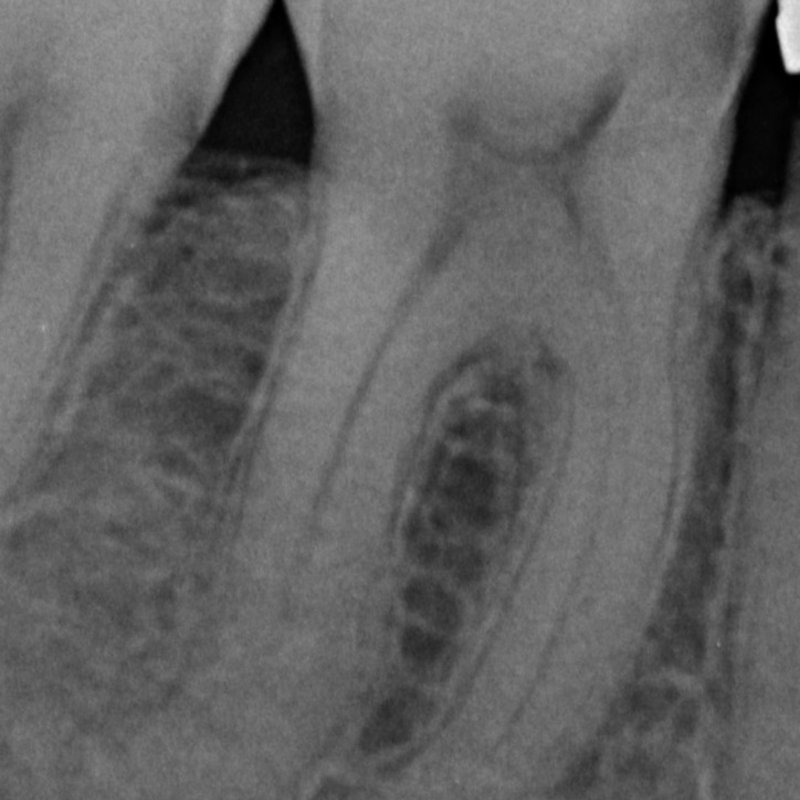

X-ray after root canal treatment

Root Canal Therapy

Endodontic treatment

Rotary endodontics with apical seal — pre- and post-treatment radiographs showing complete obturation of the canal system.